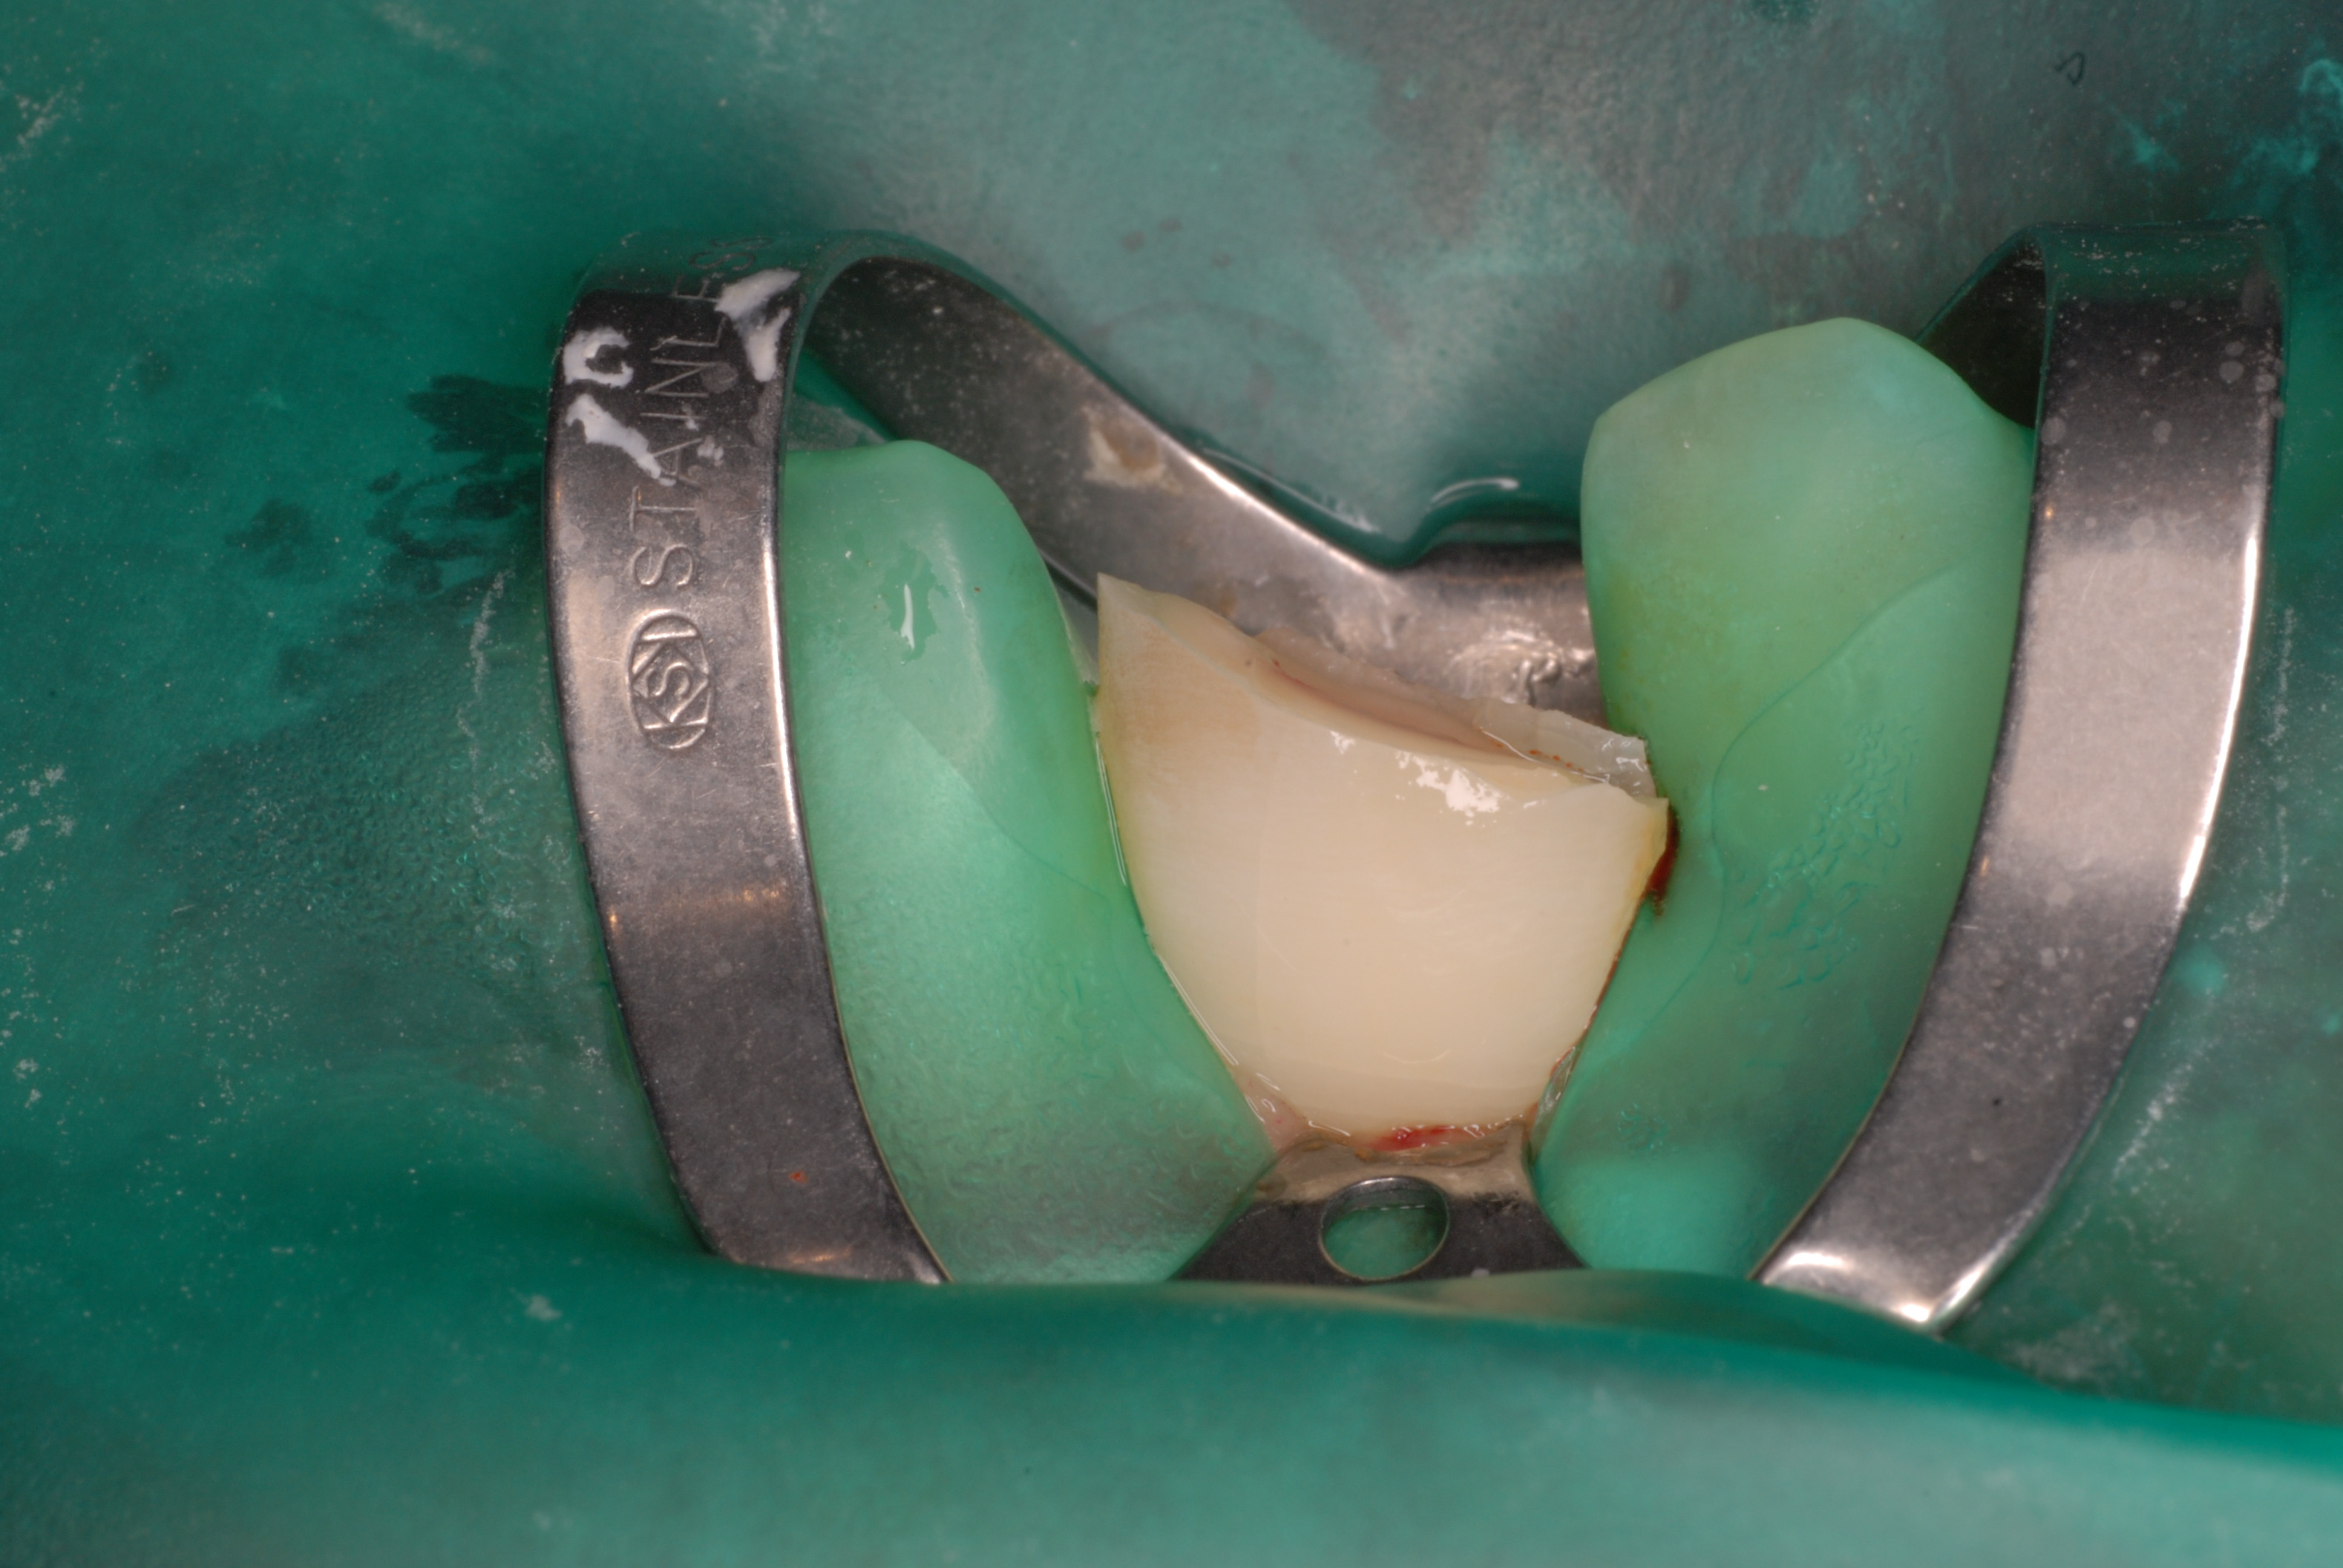

二ヶ月後ですが、歯周病が酷くなったので一時的に矯正治療を中止しました。歯周ポケットの深さを測っています。

挿入したゴムのポイントです。